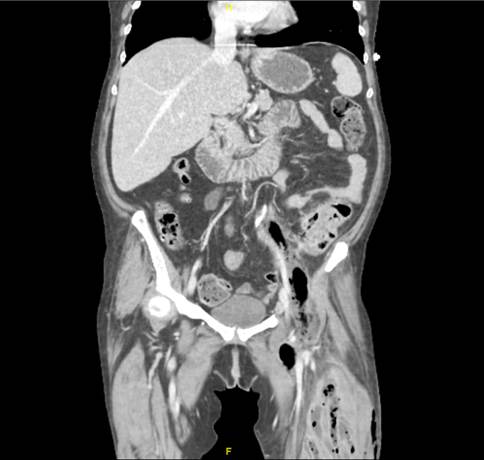

Fig. 1 Diagnóstico: Diverticulitis perforada causante de fascitis necrotizante.

La TC mostraba una colección hidroaérea en psoas y retroperitoneal que asciende hasta la cavidad abdominal hallándose una diverticulitis perforada. El tratamiento quirúrgico se basó en el drenaje de la colección retroperitoneal y sigmoidectomía, seguido de una fasciotomía, desbridamiento y lavado del muslo.